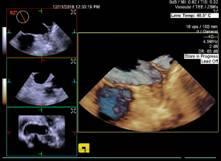

自贡市第四人民医院超声医学科自今年6月开展自贡市首例局部麻醉下经食道超声心动图检查以来,近日,该科又率先在川南开展了局部麻醉下经食道四维超声心动图检查。

患者袁先生,有心脏二尖瓣及主动脉瓣杂音。心血管内科医生怀疑二尖瓣和主动脉瓣瓣膜病。12月5日早上,在超声室行局部麻醉下经食道四维超声心动图检查,清晰显示主动脉瓣重度狭窄,钙化呈功能二叶,排除了二尖瓣瓣膜病变,给临床提供了依据。